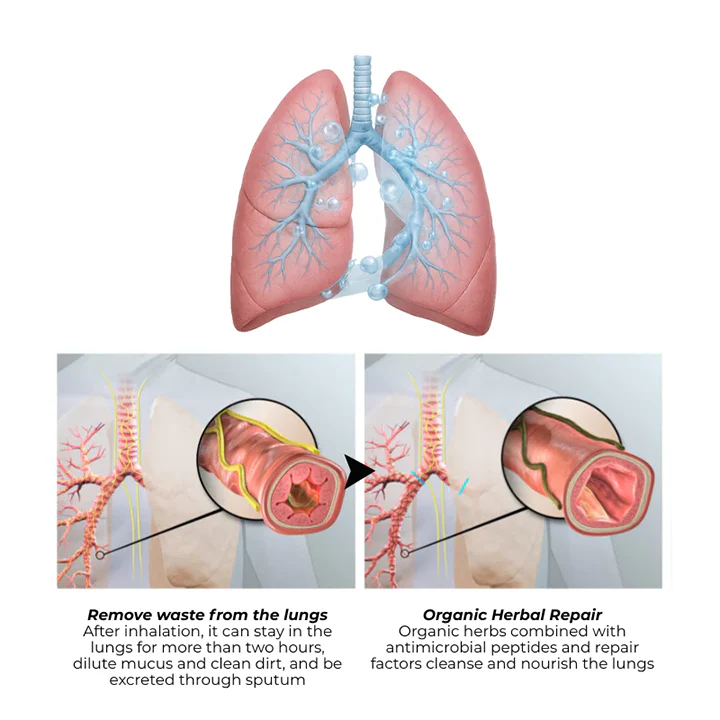

New Herbal Discovery Shows How to Help Cleanse the Lungs Naturally Without Drugs or Inhalers

Helps support healthy lung function by helping cleanse the airways and promote better breathing comfort.

Carefully formulated with powerful herbs, this natural blend supports lung cleansing and easier breathing safely.

This advanced herbal formula helps support healthy lung function and clear airways naturally.

Revolutionary Nasal Inhalation: Why 2 Minutes Beats 90 Minutes

But what if there’s a breakthrough approach that works in 2 minutes instead of 90 minutes? Timilk® HerbaAir’s revolutionary nasal inhalation technology delivers powerful mullein extract directly to your respiratory system within 2 minutes – bypassing your digestive system entirely and reaching your lungs where you need it most.

Revolutionary Nasal Inhalation Science

Traditional oral supplements deliver only 20-40% of active compounds to your lungs after passing through your digestive system. Timilk® HerbaAir’s nasal inhalation technology delivers 90-100% bioavailability directly to your respiratory system within 2 minutes.

Scientific studies confirm nasal delivery achieves 2-4 times higher effectiveness than oral capsules, drops, or patches. While oral supplements take 45-90 minutes to reach peak effect, nasal inhalation works within 2 minutes.

When you need respiratory relief, every second counts. That’s why customers experience such dramatic differences with nasal inhalation – you’re getting maximum potency exactly where you need it, exactly when you need it.

Unlike traditional supplements that take hours to work, Timilk® HerbaAir delivers a clear comfort timeline. Within 2 minutes, you’ll feel significant soothing relief as mullein extract makes direct contact with your respiratory tissues. After 2 weeks of consistent use, persistent coughing and chest tightness begin to fade noticeably. By 4 weeks, you’ll experience sustained respiratory comfort improvement – breathing freely again. This progressive support works with your body’s natural processes for long-term wellness, not just temporary relief.